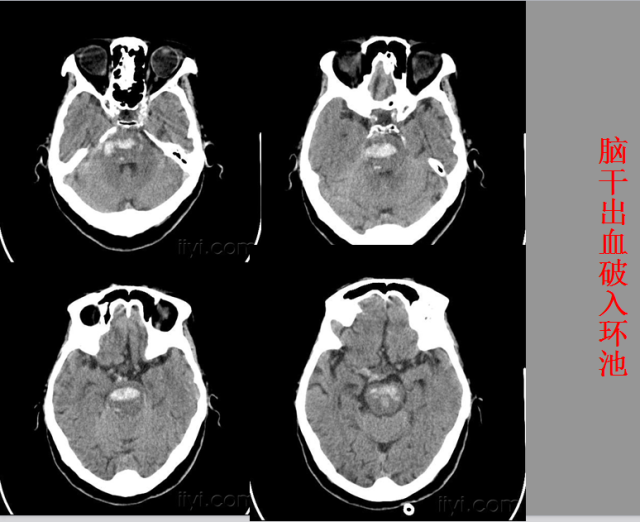

急性颅脑损伤篇

急胸症篇